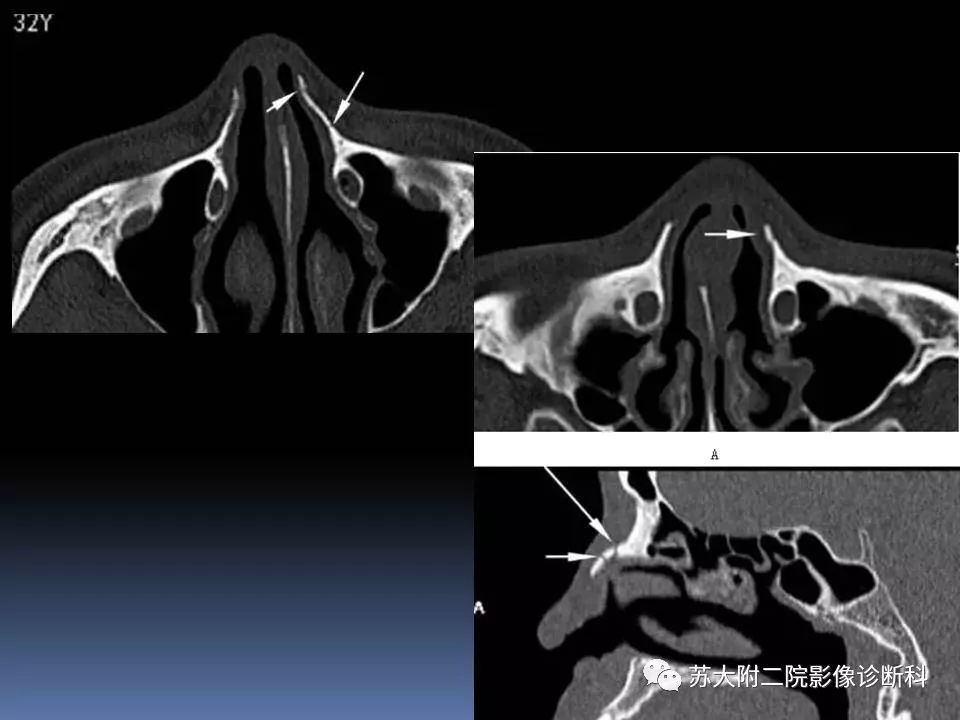

【PPT】鼻骨骨折影像诊断误区-2